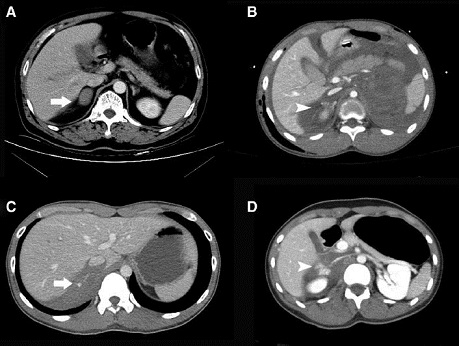

Tomografía axial computada (TAC): Es el método de elección en pacientes hemodinámicamente estables. Es rápido y altamente disponible. Es más sensible y específico que la pielografía de eliminación y ecografía o angiografía (7,8). Ante sospecha de lesiones vasculares se puede complementar con angioTAC, mejorando la definición de estas. Por último, las tasas de nefropatía inducidas por el medio de contraste son muy bajas, justificando plenamente su indicación.

Técnicamente se realiza en 3 fases:

- fase arterial, que evalúa lesión vascular y presencia de extravasación activa de contraste,

- fase nefrográfica, que demuestra las contusiones, hematomas y laceraciones del parénquima,

- fase tardía, que identifica lesiones del sistema colector y del resto del aparato urinario.

En la práctica diaria, los pacientes politraumatizados sometidos a protocolos establecidos de imágenes de todo el cuerpo (panTAC), muchas veces obvian la fase tardía, la cual no se realiza de manera sistemática. Por tanto, ante la sospecha de lesiones de sistema colector, uréter o vejiga, se recomienda la realización de esta fase (15 a 20 minutos luego de la inyección del contraste).

Todos los autores coinciden en la necesidad de realizar reevaluaciones con TAC, específicamente si aparece fiebre, se agrava el dolor lumbar, persiste la hematuria macroscópica o cae el hematocrito a pesar de las transfusiones (7). La tomografía sistemática de control a los pocos días y muy recomendada en otro tiempo, hoy se encuentra en tela de juicio. En la actualidad, solo se debiera efectuar en pacientes con traumatismos tipo 4 y 5

estables, con el fin de determinar la extravasación de orina que justifique su drenaje.

Además de la visión global que entrega el TAC, permitiendo la visualización de otros órganos abdominopelvianos potencialmente lesionados, existen elementos imagenológicos que pueden encontrarse específicamente en TGSR (Figura 6).

Los hallazgos típicos en el TAC, con o sin contraste, para un traumatismo suprarrenal, incluyen un hematoma redondo u ovalado, hemorragia irregular, obliteración de la glándula y una glándula suprarrenal uniforme. Puede asociarse además a trabeculación de la grasa retroperitoneal (espacio perirrenal) y/o extravasación activa de contraste endovenoso (22).

El hematoma suprarrenal habitualmente consiste en una masa ovalada o redondeada, con áreas de alta densidad (50-90 UH) ocupando la región adrenal, aunque también puede aparecer como un aumento generalizado de la glándula con bordes mal definidos. Con el paso del tiempo el hematoma se hace más pequeño e hipodenso. Además, suele asociarse a otras manifestaciones periadrenales como infiltración por material hemático del tejido graso periglandular y otras menos frecuentes como hemorragia en los espacios pararrenal anterior y posterior, compresión de la vena cava inferior, hematoma del músculo psoas, engrosamiento de la fascia de Gerota y desplazamiento anterior del riñón.